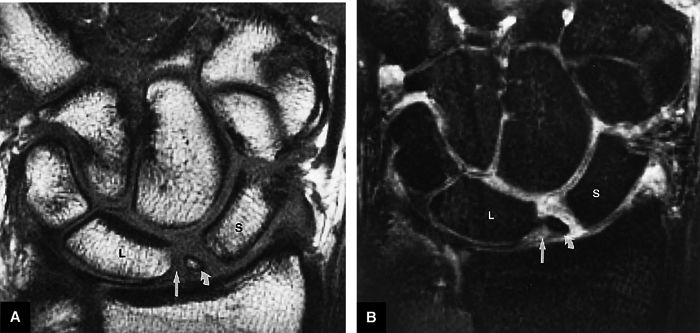

FIGURE 10.91 ● (A) T1-weighted and (B) STIR coronal images of a chronic avulsion fracture of the ulnar aspect of the scaphoid. The scapholunate ligament (straight arrow) is still attached to both the lunate and the surface of displaced scaphoid fracture fragment (curved arrow). S, scaphoid; L, lunate.